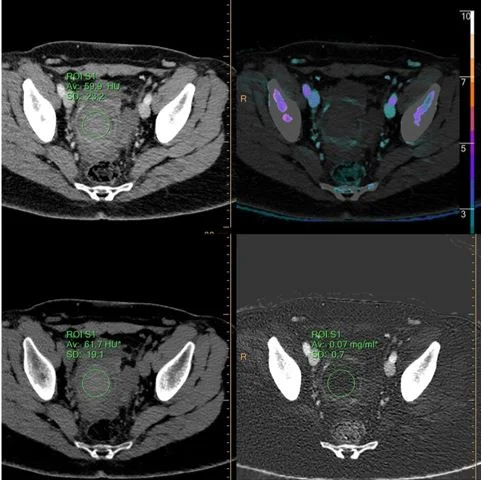

ROI on the clot shows no enhancement, and no iodine uptake.

Iodine map: No uptake in the mass. Notice the thin enhancing margin. This is a blood clot inside a cyst.

Virtual non-contrast: Dense clot in the mass.

Patient 1: Conventional CT shows right adnexal "mass”.